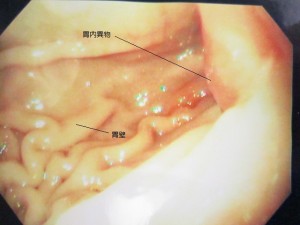

胃内内視鏡2

内視鏡中の胃内の様子です。

幽門部に異物が見えます。